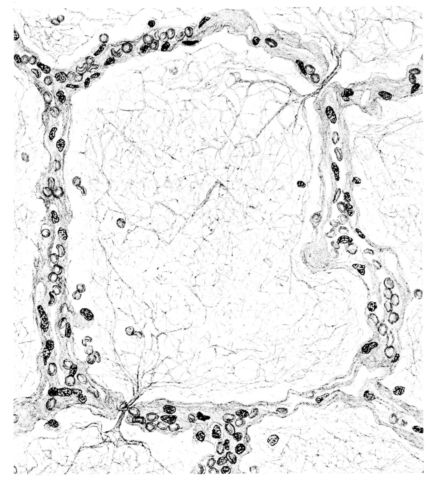

FIG. VI. AUTOPSY NO. 103. ILLUSTRATES ANOTHER EARLY BRONCHIOLAR LESION. THE EPITHELIUM IS LACKING, THE CONGESTED VESSELS OF THE SUBMUCOSA PROTRUDE INTO THE LUMEN WHICH CONTAINS DESQUAMATED EPITHELIUM, MUCUS, AND RED BLOOD CELLS.

15There is considerable evidence to support the view that the disease spreads from bronchus to bronchus, and in keeping with this view, various stages in the inflammatory processes are more readily determined in these smaller structures than in the trachea. Furthermore, it must be emphasized that even the mildest and the most extreme of these stages are not infrequently encountered in the same lung. The earliest lesion is manifested by an increased homogeneity of the protoplasm of the epithelial lining of the bronchus. The cell protoplasm loses its normal granulation and the nucleus, somewhat darker than usual, becomes conspicuous on a red base (Fig. V). In the lumen of such a tube a serous exudate, perhaps mixed with mucus, is encountered, and there is some spreading apart of the surrounding muscular tissue with engorgement of the vessels. This picture merges gradually into one where the epithelium appears as a homogeneous, red-staining ribbon, devoid of nuclei, often exfoliated, in part at least, from the underlying submucosa (92). The change is traceable through the larger bronchi, even to the ducti alveolares, and not infrequently, bacteria, either as a diffuse, minute dotting or in the form of circumscribed, colony-like formations, are spread through the red, ribbon-like strand (Fig. XVI). With the exfoliation of the epithelial lining, the submucous vessels become more and more conspicuous and may bulge into the lumen of the tube (Fig. VI). That they actually weep into the lumen is proved by the presence of red blood cells in the exudate, now rich in mucus, broken-down nuclei, and desquamated cells. The necrotizing process may not extend deeper than the epithelial lining as is the status described above (140, 162), but it also frequently involves the underlying submucous and muscular layers, so that these lose their identity and stand out as homogeneous masses, in which fragmented nuclei and bacterial accumulations are prominent. Such deeper necrotizing areas may be focal (Fig. VII), or may involve the entire circumference of the tube (Fig. VIII). Occasionally, the epithelium, now dead and staining homogeneously, is lifted from the underlying submucosa in the form of a blister (66), and has very much the same appearance as the well known, early reaction which follows the application of croton oil to the rabbit’s ear. Where this occurs, the submucosa is less involved, as though the necrotizing agent had not penetrated to the same depth and the serous reaction beneath were actually a beneficent exudate. These blisters are in contrast with the deeper areas where the fibrinous mass, mixed with the dead tissue, forms an intensely staining ring or band, which extends through the bronchiolar wall even to the surrounding alveoli.

As might be expected from the gross appearance, the alveoli vary in size. At times slightly collapsed and at other times overdistended, their lumina are still the seat of the inflammatory exudate, although the mechanical change may allow of some variation in the appearance of their walls. As a rule, however, the alveolar wall is prominent and owes its conspicuousness to the tortuous, engorged vessels within. These vessels contain red blood cells almost exclusively, and on account of the partial, occasionally complete, loss of the lining epithelium, the alveolar wall appears as a huge, dilated arteriole (101) separating the lakes of coagulated material in the spaces (Fig. XXIII). There are areas, as indicated above, where the alveolar content may be more definitely arranged in the form of beaded or homogeneous strands of different caliber; the smallest resemble delicate threads. They tend to converge toward the alveolar wall like wheat in a sheaf, and often pass through this wall by way of the so-called pores of Cohn; as soon as the body of the neighboring alveolus is reached, they again present a fan-like expansion into innumerable, fine strands (Fig. XXII). Where the exudate is more fibrinous, the alveolar wall is less likely to be distended, its vessels are not so prominent, and their content of red blood cells is definitely decreased. Still this is not the most extreme type of alveolar exudate met with at this stage. Perhaps, the most striking, although not the most frequent, exudate has a superficial resemblance to a huge, red blood clot, and it may be difficult to make out the alveolar walls separating the masses of well preserved red blood cells that fill the alveolar spaces. These areas are indistinguishable from infarcts and may be associated with thrombotic arteritis in near-by pulmonary vessels (47) (Figs. XXIV and XXV). Among the red blood cells an occasional strand of fibrin, a desquamated alveolar epithelial cell, and rarely a polymorphonuclear leucocyte may be encountered. The alveolar wall itself varies in the definition of its outline. When its vessels are greatly distended, when its alveolar epithelium is gone, and when its content consists largely of red blood cells, it is difficult to distinguish from the exudate which it encloses. However, when it is more compressed or when its epithelial lining cells are still more or less intact, it may be seen as a blue-staining strand under the low power of the microscope, for the well preserved nuclei lend it prominence.